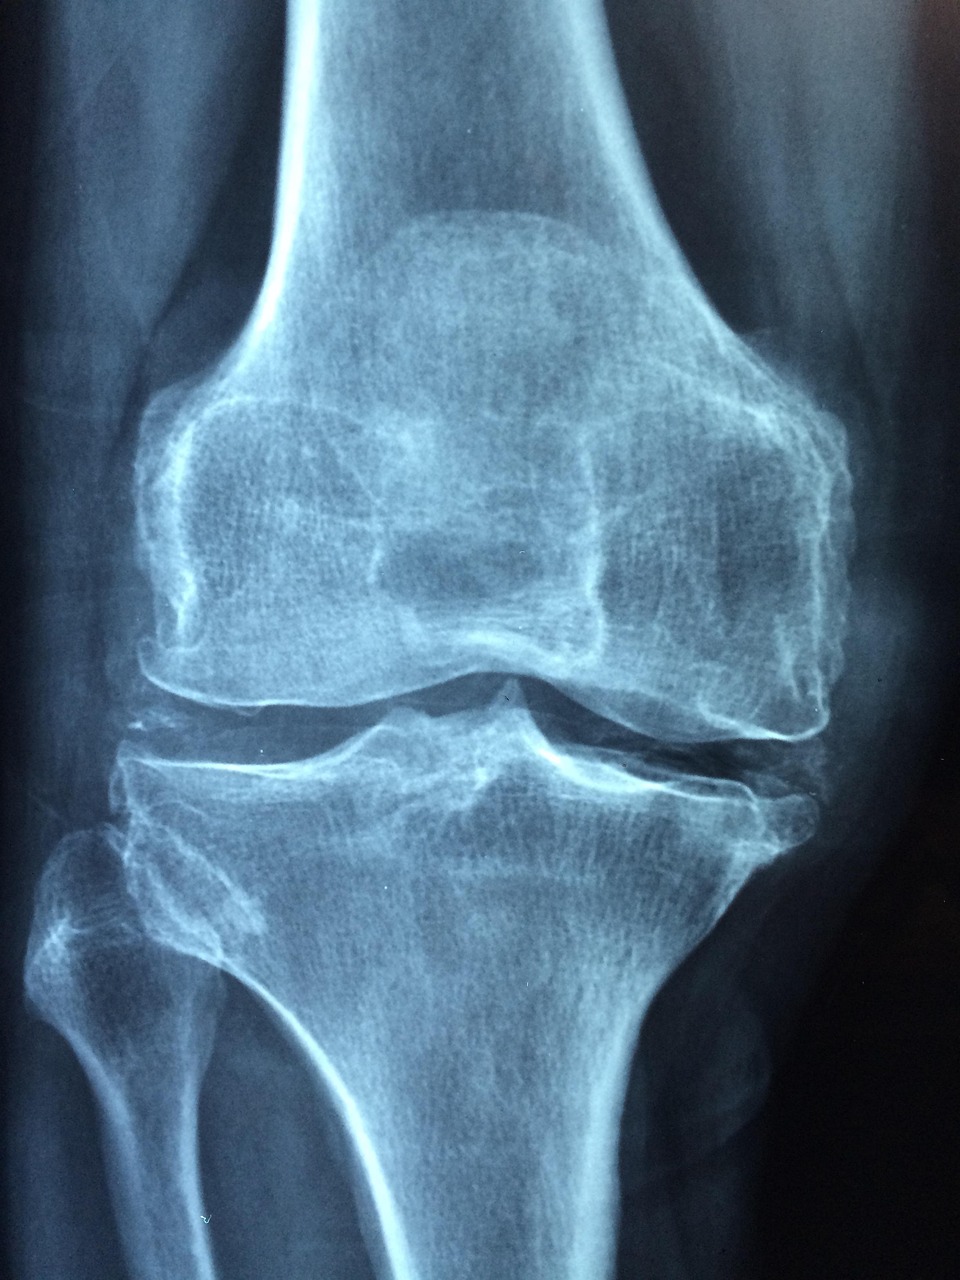

골다공증은 뼈의 밀도가 감소해 뼈가 약해지는 질환입니다. 특히 50대 이후에는 호르몬 변화와 함께 뼈 손실 속도가 급격히 빨라집니다.

문제는 통증이나 불편함 없이 진행된다는 점입니다. 골절이 발생한 후에야 발견되는 경우가 많아 조기 검사가 중요합니다.

골다공증 검사는 현재 뼈 상태를 객관적으로 확인할 수 있는 가장 확실한 방법입니다. 단순한 노화인지, 치료가 필요한 단계인지 구분할 수 있습니다.

검사를 통해 골밀도 수치를 확인하면, 정상·골감소증·골다공증 단계로 나뉩니다. 이 결과에 따라 운동, 영양 관리, 약물 치료 여부가 달라집니다.